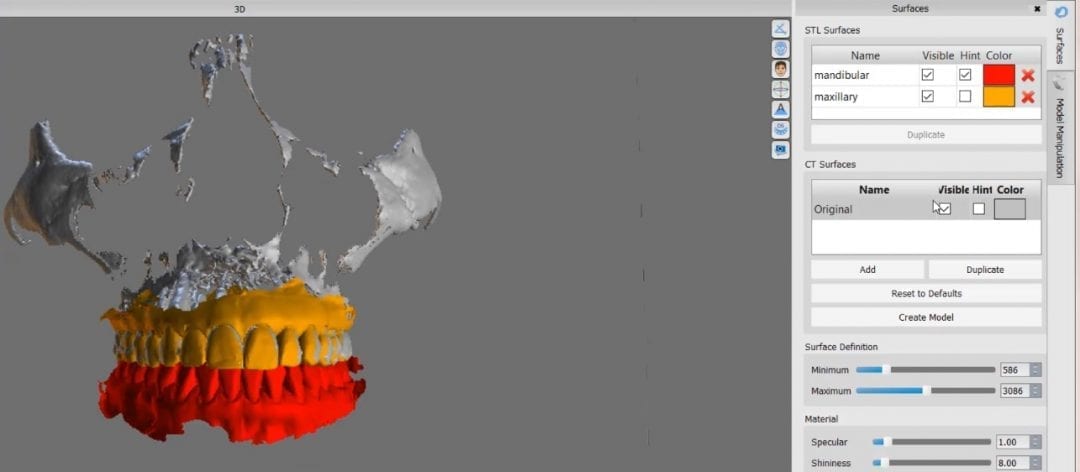

August 1, 2018In this particular clinical case, the patient has opted to utilize clear aligners to straighten some anterior crowding. The Medit i500 was used to capture both the upper and lower […]